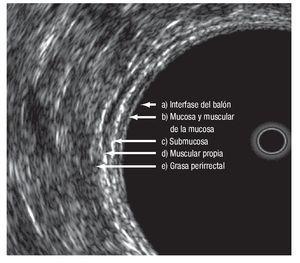

Las modalidades de imagen para la etapificación preoperatoria del cáncer rectal son el ultrasonido transrectal (UTR), la tomografía computarizada (TC) y la resonancia magnética nuclear (RM). El UTR es la técnica más utilizada para evaluar la profundidad de invasión de la pared rectal, con una sensibilidad y especificidad de 94% y 86% respectivamente; y de 94% y 69%, para la invasión del tejido perirrectal17,18 (Figura 1). La exactitud global del UTR para evaluar la T oscila de 80% a 95%.19-25 La RM con bobina endorrectal ofrece las ventajas de permitir mayor campo de visión, no es operador dependiente y evalúa tumores que causan estenosis. La etapificación T con este estudio tiene una exactitud que va de 50% a 95%.26-32

¿ Figura 1. Capas del recto evaluadas por medio de ultrasonido endorrectal.